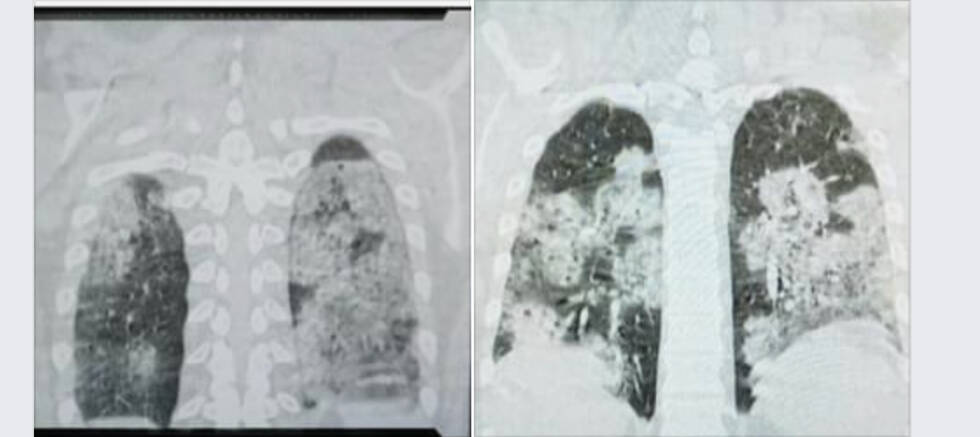

Doktor Stevanović na svom Facebook profilu objavio je CT pluća jednog od pacijenata, mladog čovjeka koji je nepušač i koji je bio zdrav prije infekcije koronavirusom.

“Za one koji ne znaju, zdrav je crni dio pluća. Doktori, neznalice, peta kolona, diktatori itd. posegnuli su za slamku spasa i ordinirali lijek koji je pacijent kupio. Oporavlja se”, poručio je doktor Stevanović i dodao:

“Lijek je skup i ne može se nabaviti na teret zdravstvenog osiguranja. I svi ostali hospitalizirani bolesnici imaju upalu pluća. Nadati se da će što manje njih imati ovako tešku. I vi, dragi sugrađani, možete pomoći da što manje naših građana oboli.”